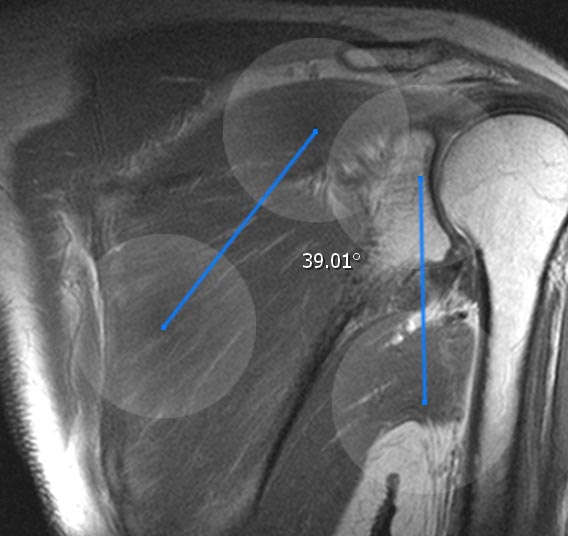

11.1.5. Winkelmessung

Die Winkelmessung erzeugt einen Winkel auf dem aktuellen Schnittbild. Die Geraden des Winkels sind in ihrer Länge und Richtung einstellbar, sodass Sie den Winkel nach Belieben ausrichten können. Sie können den gesamten Winkel durch antippen und halten des Schnittpunktes verschieben. Der Winkel kann im Annotationsmenü gelöscht werden.

Neben dem normalen Winkel gibt es auch den entfernten Winkel. Während der normale Winkel ein echter Winkel ist, berechnet der entfernte Winkel den Winkel zwischen den beiden Geraden, ohne einen Schnittpunkt. Darüber hinaus kann es wie ein normales Winkelwerkzeug verwendet werden.